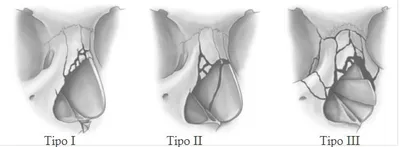

Fratura Le Fort ou de Maxilar

São fraturas que ocorrem em diferentes níveis da face, divididas em três tipos principais (Le Fort I, Le Fort II e Le Fort III), cada uma afetando diferentes regiões do rosto. Essas fraturas são frequentemente o resultado de traumas graves e podem causar deformidades faciais significativas, dificuldade para respirar e até mesmo comprometimento da via aérea.